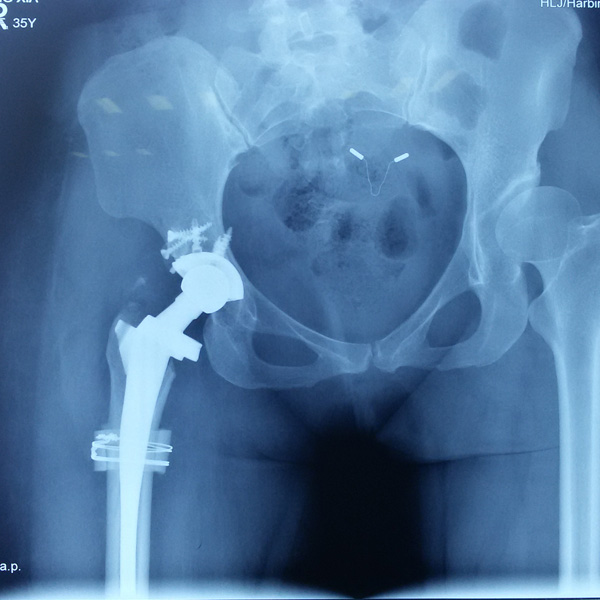

先天性髖關(guān)節(jié)脫位

患者王某某,女,41歲,從會(huì)走路以來(lái)就發(fā)現(xiàn)一條腿長(zhǎng),一條腿短,也就是人們俗稱(chēng)的“跛子”,之前雖然兩條腿長(zhǎng)短不一,但起碼還可以走路,維......